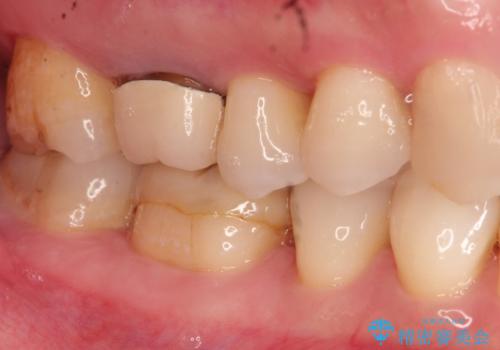

やはり内部では少量の虫歯がありましたので、拡大鏡使用して虫歯を除去しました。

虫歯の取り残した場合は将来的に再治療が高い確率で必要となります。

今回精度の高い治療を行うことで、再治療の可能性を限りになく小さくできました。